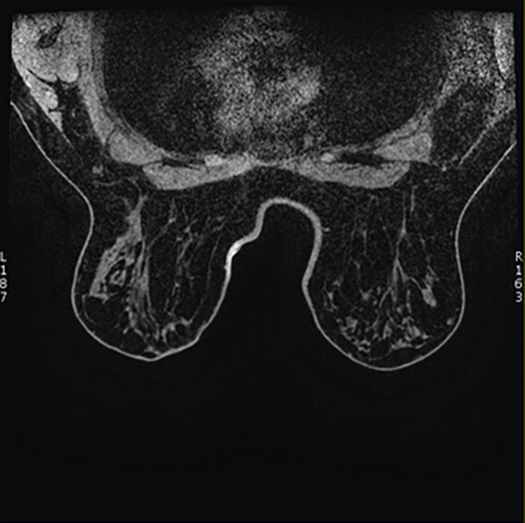

Figure 1. Axial Breast Images Presentation: Supine

- If you choose Prone, the system displays images with the prone orientation.

Figure 2. Axial Breast Images Presentation: Prone